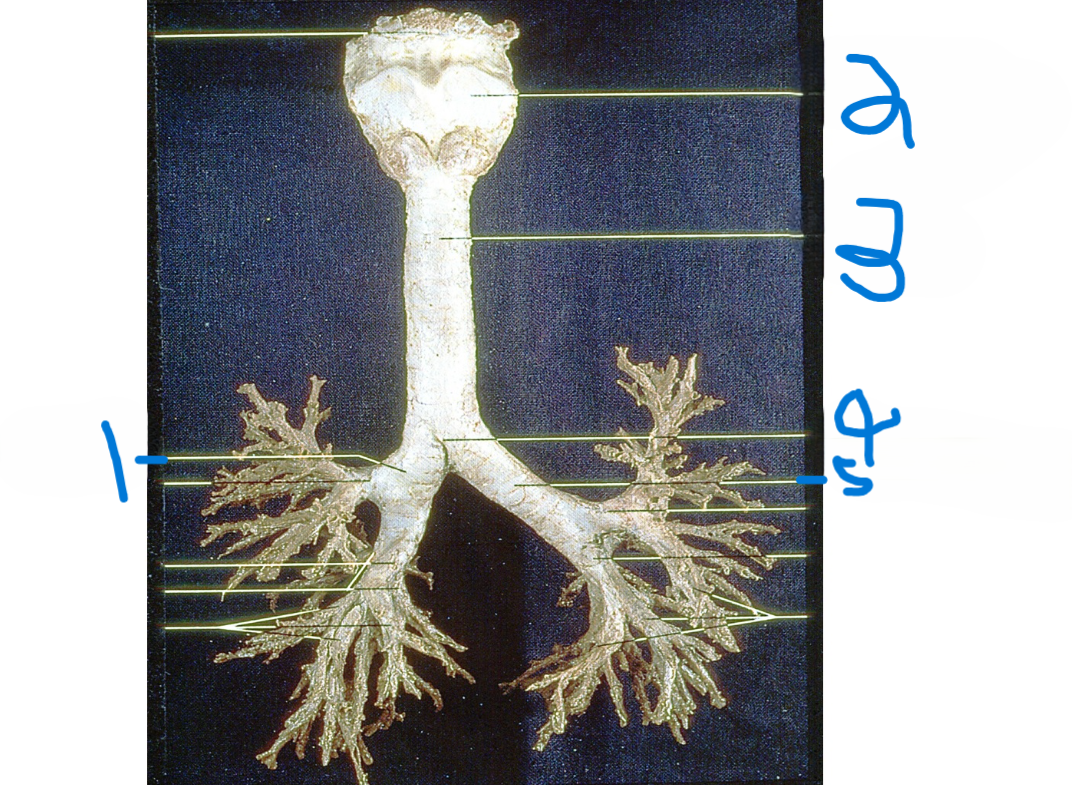

Right main bronchus

What is depicted by #1

Thyroid cartilage

What is depicted by #2

Trachea

What is depicted by #3

Carina

What is depicted by #4

Left main bronchus

What is depicted by #5